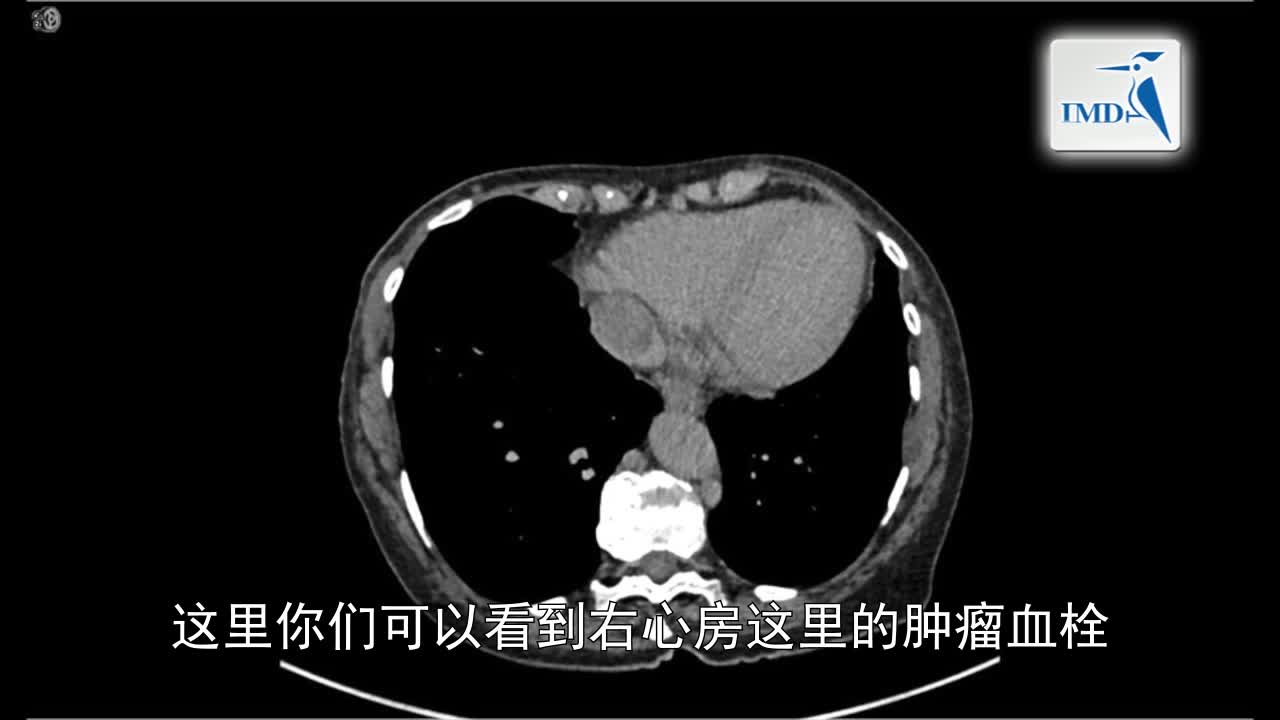

治疗心肾肿瘤中的当代开腹手术技巧